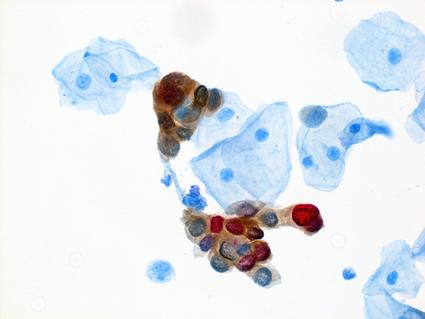

Nicolas Wentzensen, M.D., Ph.D., M.S., senior investigator and Deputy Director, Clinical Genetics Branch, discusses the recent FDA approval of self-collection kits for use in clinics for cervical cancer screening. His interview was published in the NCI Cancer Currents Research Blog.